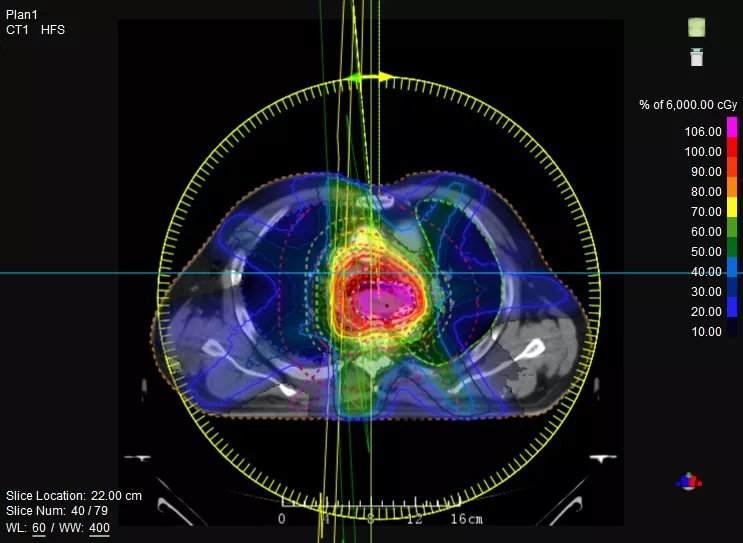

機載CT影像可直接用于放療計劃制作

CT-IGRT配準,除骨性標記外,還能以器官、軟組織等作為參考,真正找到配準目標

鼻咽癌患者,進行旋轉容積調強治療(uARC)

一體化CT-linac讓自適應放療ART概念變?yōu)楝F實?;颊呷煶虪顟B(tài)監(jiān)控,適時在線調整治療計劃,精準控制治療劑量,為患者動態(tài)定制個體化治療方案。uAI賦能智能勾畫和自動計劃,秒級勾勒靶區(qū)和危及器官,大幅縮短自適應放療時間。

聯(lián)影CT-linac全程監(jiān)測治療過程病灶的變化,及時調整和優(yōu)化治療方案